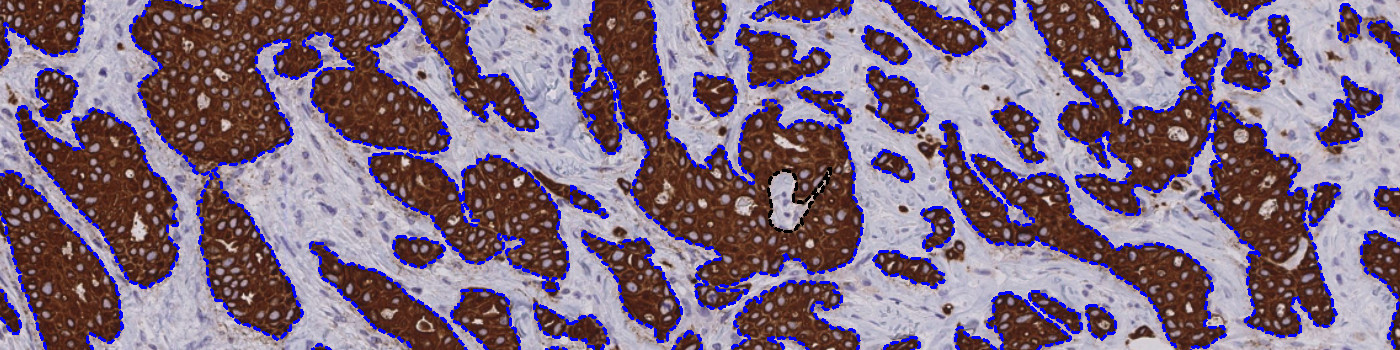

The output consists of one or more ROIs, outlining the tumor areas. The output variable obtained from this protocol is:

Second, the tumor areas are automatically detected from the PCK slide and outlined as regions of interest (ROIs) (see FIGURE 4 and 5). The ROIs are then superimposed on the aligned ER/PR/Ki-67 tissue slide to outline the tumor region for subsequent analysis limited to the inside of the tumor regions.